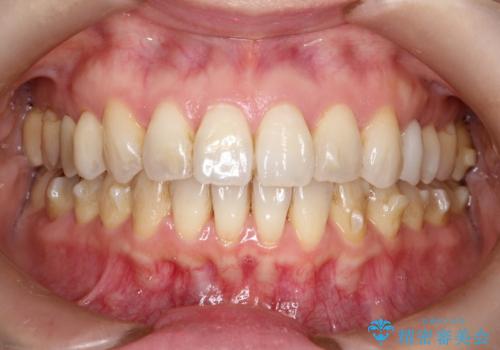

【インビザライン 】前歯を下げたい

- 前歯の凸凹と、前突を主訴に来院されました。

インビザライン にて治療を行なっております。

治療期間中はゴムかけを行なってもらうことで、前歯を下げることができました。